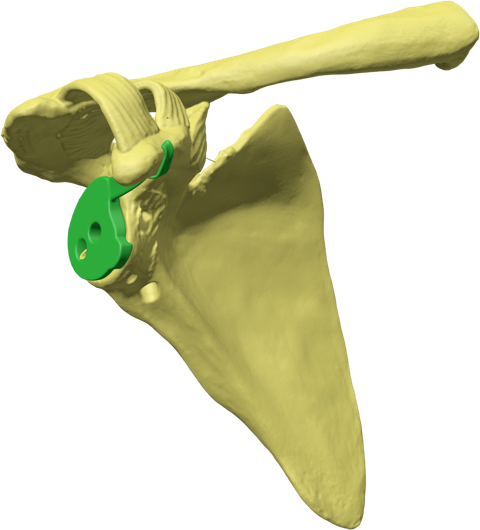

Glenoid Fixation Challenge - Patent No. - US11918476B1

Our innovative design restores anatomic mechanics through enhanced glenoid implant fixation. Using patented Patient Match technology, CT data generate implants matched to variable scapular anatomy, providing immediate fixation that counteracts early rehabilitation forces and supports bone ingrowth into a porous surface for permanent fixation. Improved fixation enables mechanical constraint, supports anatomic shoulder replacement designs, improves motion, and reduces dislocation risk.

The proposed solution, Anatomical Rotator Cuff Arthroplasty (ARCA), reflects unprecendented potential to restore normal shoulder biomechanics for patients requiring joint replacement.